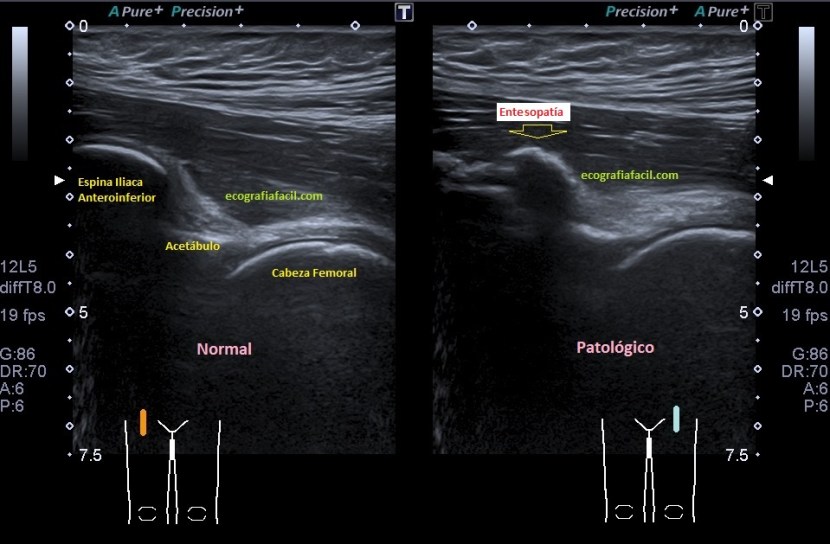

Evidentemente es una imagen patológica comparada con una normal contralateral, la anatomía de la región patológica está cambiada, el hueso está irregular, comparativamente con la zona normal. Esos cambios en el hueso se visualizan en la espina iliaca inferior, donde inserta el tendón del recto anterior, pero este tendón no solo inserta fibras ahí, sino que algunas de ellas insertan justo en la región superior del acetábulo,imagen 3, es decir, justo antes de la inserción en la espina iliaca anteroinferior, algunas se bifurcan hacia profundo, buscando el acetábulo.

La imagen 2 es centrándonos en la zona de patología, aún más espectacular. Se observa la deformación global del hueso en esa zona marcado con flecha amarilla plana.

Explorar esta zona de inserción es complejo, el recto anterior, que luego es el tendón intramuscular o rafe del recto anterior del cuadriceps, inserta mediante su tendón buscando la profundidad en la cadera, con lo que encontramos anisotropía…te voy a enseñar una forma de explorarlo donde vas a poder corregir esa anisotropía. La exploración habitual es con la pierna en extensión y decúbito supino, pero vamos a pedir al paciente que se siente en la camilla, baje la pierna y apoye el talón del pie, el tronco del paciente mínimamente inclinado hacia atrás, la cadera y la rodilla en extensión y la sonda colocada en la zona de inserción…la imagen que logras es esta maravilla, imagen 3.

Cuando en la zona de inserción en la EIA inferior tiene cambios en la inserción del tendón se verán imágenes de calcificación lineal de la inserción, cuando esos cambios son muy llamativos tenemos la imagen 1 y 2, cuando son menos llamativos la imagen 4, pero ojo que ambos pueden dar clínica a valorar por los médicos especialistas.